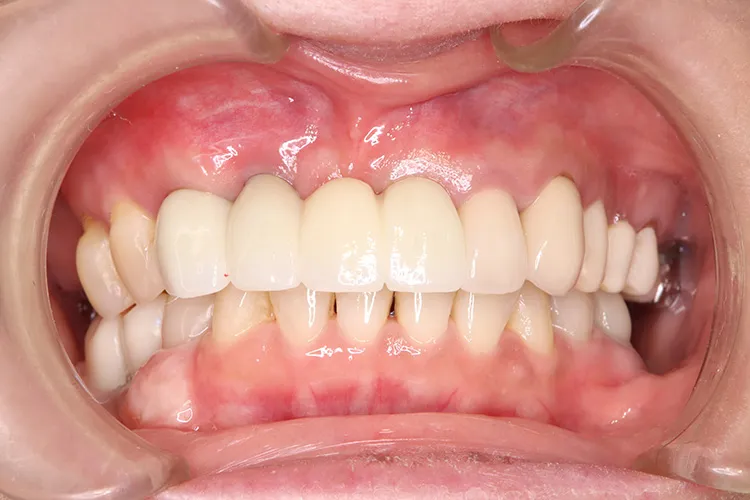

歯ぎしり・食いしばりが強い方の治療ケースです。全体的に歯が擦り減り正面から見て下の歯が見えないほど噛み合わせの高さが失われており、顎関節にも症状がでていました。ヒビが入って保存不可の歯を抜歯しインプラントを計5本埋入し、前歯・臼歯にインプラント土台のブリッジを入れることで噛み合わせの高さを回復しました。古い金属の被せ物もジルコニアでやりかえました。噛み合わせの高さが改善したことで顎関節症状もなくなり快適に過ごされています。歯ぎしりがある方は、夜間のナイトガード装着が必要になります。